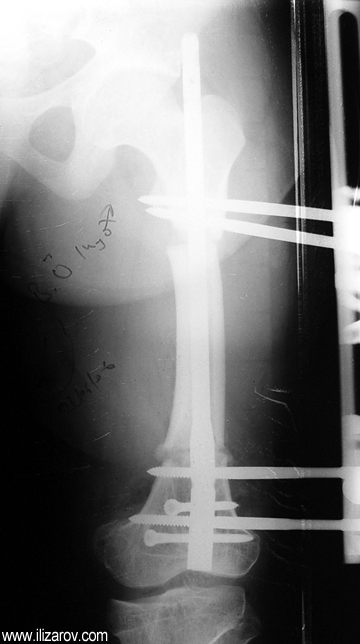

Because the deformity caused by hypophosphatemic rickets is very close to the growth plate, a significant deformity and malalignment occurs. For that reason, more than one deformity centers (CORA) are found at preoperative evaluation, and osteotomy at more than one level is required to correct the deformity. The most frequently used methods to correct the deformity are acute or gradual deformity correction using the Ilizarov method or unilateral external fixator. In the ‘fixator assisted nailing’ technique, which is applied in our department, the deformity is corrected in an acute fashion with the help of an external fixator, and the extremity is stabilized by an intramedullaru nail. The external fixator is removed before the end of the surgery if no gradual lengthening is planned postoperatively. If lengthening (over nail) is planned, the fixator is removed after the completion of the lengthening procedure. As a result, the risk of pin tract infection is eliminated, correction loss and relapsing of the deformity (which are important problems in the treatment of hypophosphatemic rickets) are avoided, eary motion and full weight bearing are allowed, and comfortability of the patient is improved because the duration with external fixator is decreased.

Case 1